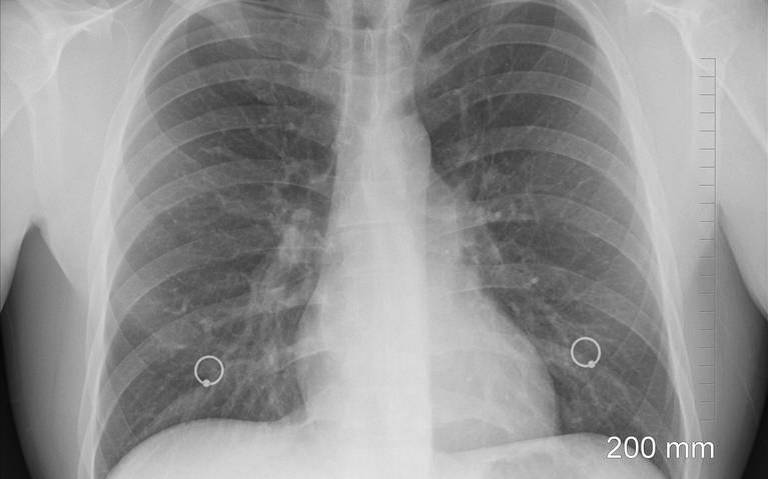

Médicos coinciden por un lado que la neumonía es la inflamación o hinchazón del tejido pulmonar, debido a la infección causada por un germen. Sin embargo, en el caso de la neumonía atípica, la infección es causada por bacterias diferentes de las que son más comunes que causen la neumonía típica. La neumonía atípica también tiende a provocar síntomas más leves que la neumonía típica.